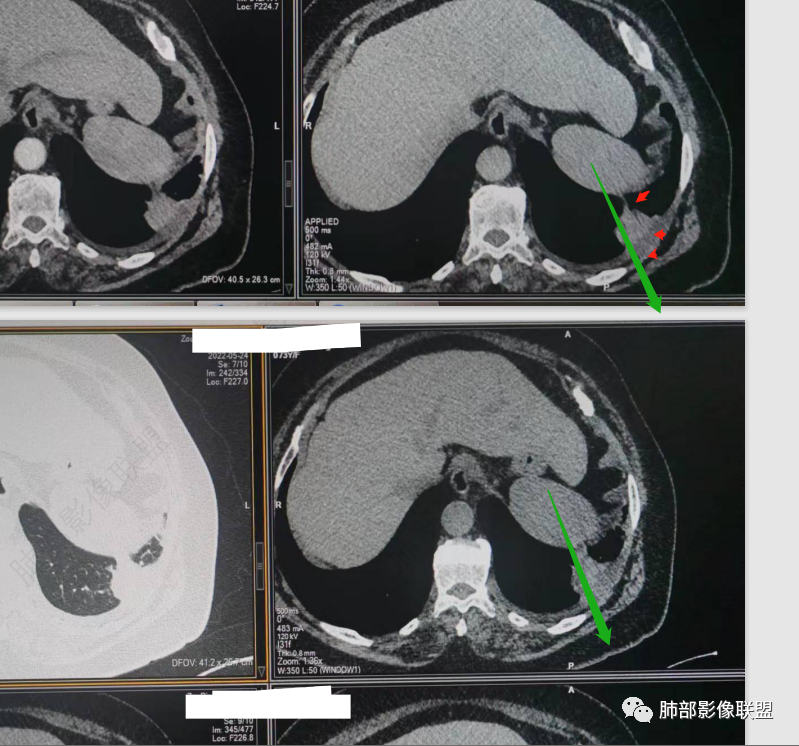

南边:今天的病例肺内部分基本都是炎性特点,问题就在于胸膜。

糊墙:肺内病灶不侵犯壁层胸膜或以外,与壁层胸膜相对而言分界清楚。

栽赃:病灶侵入壁层胸膜及胸膜外脂肪间隙、胸壁其他结构等,相对在病灶中央区域,与胸膜分界不清。

南边:看肺内病灶与胸膜分界清,增强后强化不一致,需要综合分析。

这是糊墙。

这就栽赃。都突到外面去了。

看看这个,骨头都侵袭了。

今天的病例有些伪影。

看起来就觉得放射状伪影。

我就不知道这些是胸水,伪影导致密度增高?还是胸膜增厚?

我只是邓较瘦:今天平扫的像栽赃, 增强感觉是增厚的胸膜。

南边:一般这类侵袭,是中央地带毛刷状延伸到胸膜内。

而且旁边这么宽的少,所以觉得很奇怪,不太符合,我是怀疑与照片有关。

你对比一下两侧的密度。肌肉密度不一样。

我只是邓较瘦:南大这个我感觉局部似乎是栽赃呢 箭头那里是啥?

南边:栽赃是这样过去的,中间不会脂肪间隙清晰。

胸壁的组织,除非你怀疑胸壁转移结节。

转移淋巴结。

局部侵犯。有差异。

我只是邓较瘦:这个是侵犯出去不是淋巴结吧?

南边:不是,你看看强化与淋巴结不一致。

我只是邓较瘦:强化与肿瘤差不多。

南边:是。